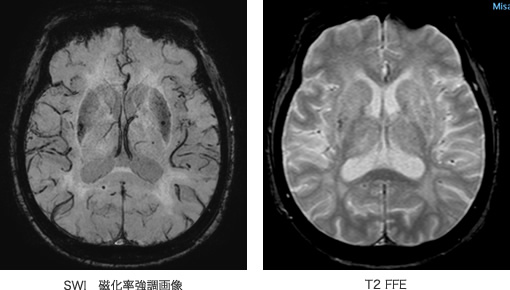

画像例(頭部領域 SWIによる微小出血の検索、梗塞or出血の鑑別)